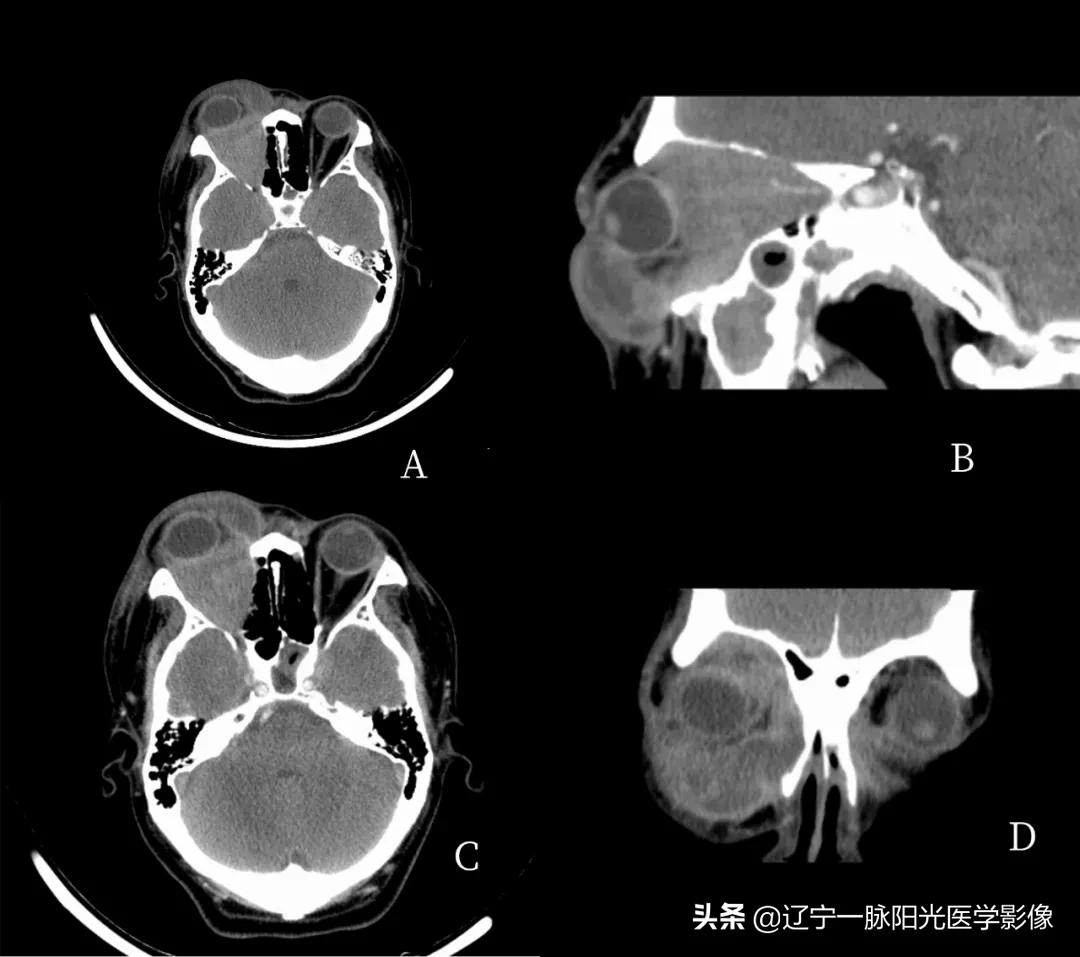

影像所见:

图 A、C 轴位及冠状位示右侧眼睑及球后软组织肿胀,脂肪间隙不清,见混杂稍低软组织密度影,增强扫描轻度强化

图 A、B、D 轴位、冠状位示右眼眶内球后肌椎内软组织填充,边界不清,密度不均,肌椎内病灶范围约为 4.1x3.2 cm,与眼环相比呈等密度,图 B、D 示增强扫描后病灶可见轻度强化

图 D 冠状位示右眼球受推外突,病灶包绕右侧视神经及眼肌,视神经及眼肌显示不清,肌肉间隙消失

影像诊断:右眼改变,考虑蜂窝组织炎伴眶内炎性假瘤形成